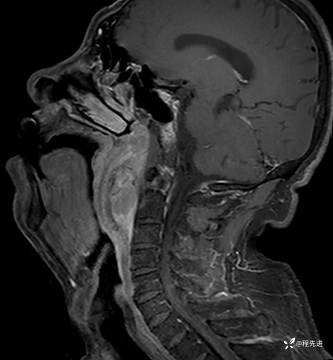

MRI平扫+增强:

T1增强: